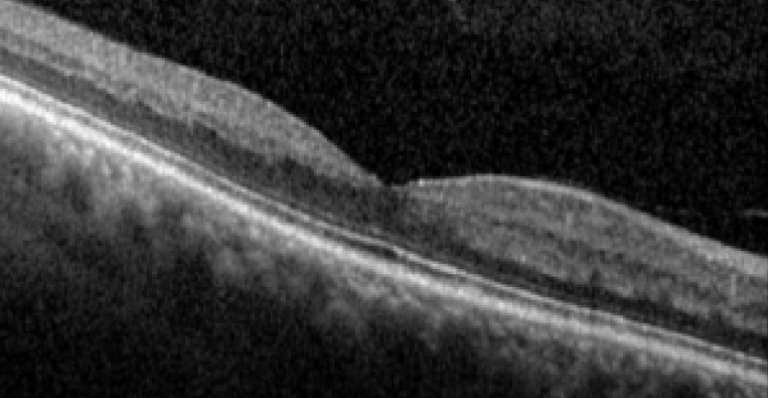

La mejora básica del proceso en la clínica de retina implica varias acciones. En primer lugar, las vías de flujo del paciente se identifican y evalúan para determinar si se ejecutan en serie, en paralelo o en combinación con algunos pasos de proceso comunes; estos pasos comunes tienen un mayor riesgo de formación de cuellos de botella. Por ejemplo, si los pacientes nuevos, las revisiones y a los que acuden para control de terapia intravítrea convergen en la OCT, entonces la posibilidad de formación de cuello de botella en la OCT es alta. Utilizando un enfoque Lean, se evalúan las vías para eliminar posibles recursos desperdiciados, como personal innecesario o excesivo, movimientos de pacientes o pasos redundantes. Es importante cuantificar los tiempos de espera para tener claro el alcance del problema. Los tiempos de flujo del paciente se analizan para identificar objetivamente las tareas y las vías de atención que consumen los mayores tiempos. Estas tareas y vías se priorizan para posibles mejoras operativas. Las mejoras operacionales pueden incluir la reconfiguración de la oficina para eliminar el movimiento innecesario del personal o del paciente, o salas de exámenes adicionales o personal para aumentar la capacidad en los cuellos de botella. La optimización de la citación en cuanto a la utilización de la sala, el personal o las características del paciente también pueden mejorar el flujo del paciente. Por ejemplo, la vía del paciente de inyección intravítrea utilizaría su propia sala de espera, personal, salas de examen y equipo de diagnóstico; estas mejoras disminuirían la variación y limitarían la formación de cuellos de botella.